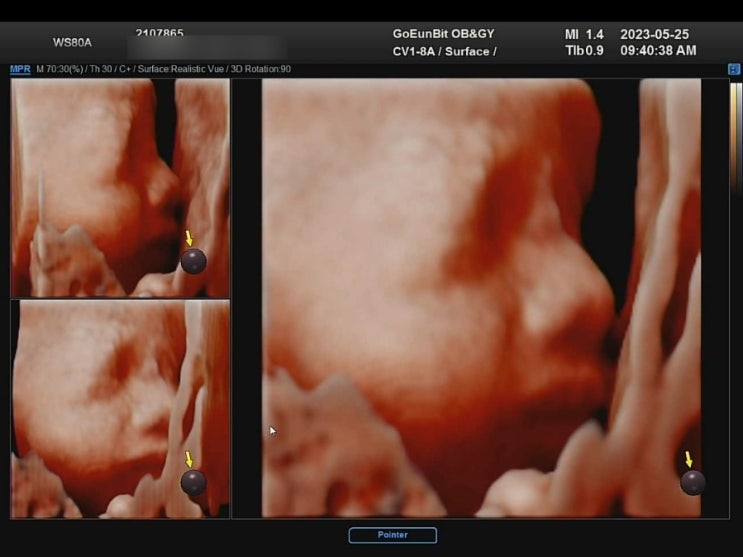

[28주0일] 입체초음파 보고왔어요 :D (@강동고은빛)

2023.05.25 28주 0일. 오늘은 입체초음파를 보는 날이에요. 입체초음파는 보통 27주~30주 사이에 보는데, 2...